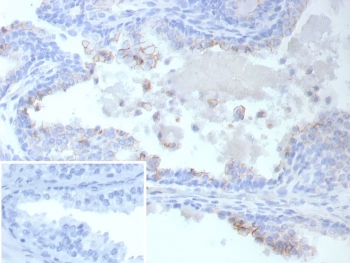

IHC staining of FFPE human prostate cancer tissue with ABCC4 antibody (clone ABCC4/9019). Inset: PBS used in place of primary Ab (secondary Ab negative control).